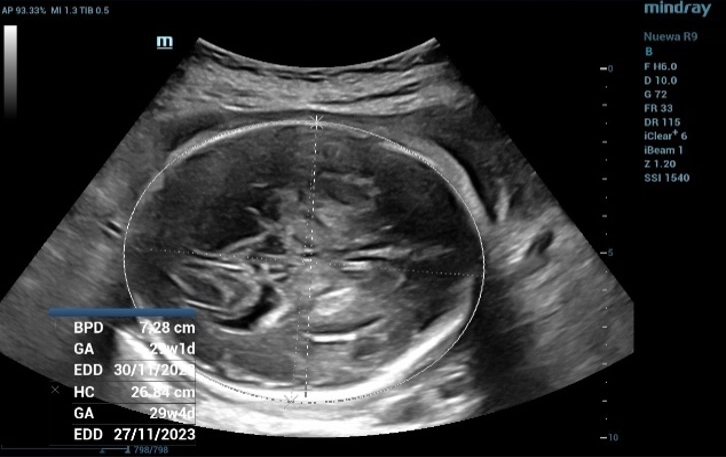

Fetal Head Biometric Measurements: Biparietal Diameter (BPD)

Figure 1 Fetal Head Biometric Measurements: Biparietal Diameter (BPD). BPD is used to estimate fetal weight and determine gestational age

The measurement of Biparietal Diameter (BPD) (Figure 1) and Femur Length (FL) (Figure 2) demonstrated a close approximation to the actual gestational age. However, when assessing the Abdominal circumference (AC), it was observed that the measured gestational age exceeded the actual gestational age due to the presence of fluid accumulation around the fetal abdomen (Figure 3).